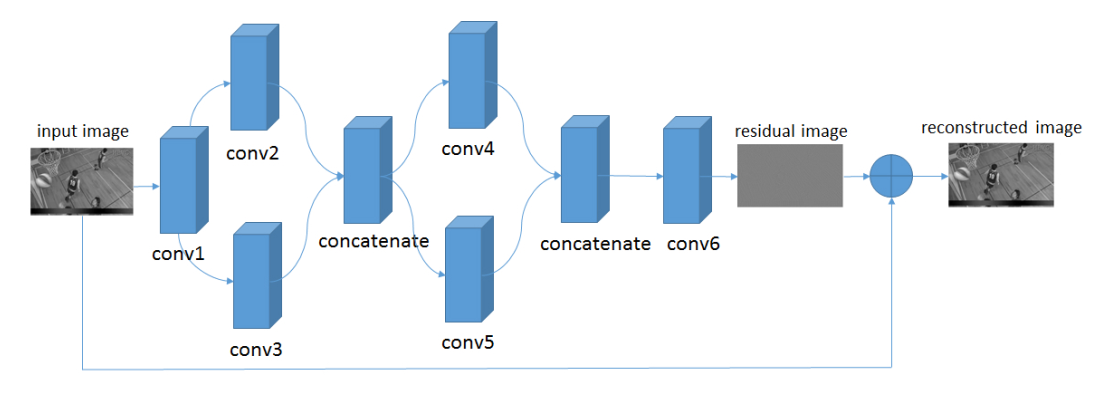

return x10.2、VRCNN

In [24]

# 定义模型结构

class VRCNN(nn.Layer):

def __init__(self):

super(VRCNN, self).__init__()

self.conv1 = nn.Sequential(

# 定义一个卷积层conv1,输入通道是1,输出通道64,卷积核大小为5,步长为1,padding为2,使用relu激活函数

nn.Conv2D(1, 64, 5, stride=1, padding=2),

nn.BatchNorm(64),

nn.ReLU(),

)

self.conv2 = nn.Sequential(

# 定义一个卷积层conv2,输入通道是64,输出通道16,卷积核大小为5,步长为1,padding为2,使用relu激活函数

nn.Conv2D(64, 16, 5, stride=1, padding=2),

nn.BatchNorm(16),

nn.ReLU(),

)

self.conv3 = nn.Sequential(

# 定义一个卷积层conv3,输入通道是64,输出通道32,卷积核大小为3,步长为1,padding为1,使用relu激活函数

nn.Conv2D(64, 32, 3, stride=1, padding=1),

nn.BatchNorm(32),

nn.ReLU(),

)

self.conv4 = nn.Sequential(

# 定义一个卷积层conv4,输入通道是48,输出通道16,卷积核大小为3,步长为1,padding为1,使用relu激活函数

nn.Conv2D(48, 16, 3, stride=1, padding=1),

nn.BatchNorm(16),

nn.ReLU(),

)

self.conv5 = nn.Sequential(

# 定义一个卷积层conv5,输入通道是48,输出通道32,卷积核大小为1,步长为1,padding为0,使用relu激活函数

nn.Conv2D(48, 32, 1, stride=1, padding=0),

nn.BatchNorm(32),

nn.ReLU(),

)

self.conv6 = nn.Sequential(

# 定义一个卷积层conv6,输入通道是48,输出通道1,卷积核大小为3,步长为1,padding为1,使用relu激活函数

nn.Conv2D(48, 1, 3, stride=1, padding=1),

nn.BatchNorm(1),

)

self.relu = nn.ReLU()

# 定义网络的前向计算过程

def forward(self, inputs):

inputs = F.interpolate(x=inputs, scale_factor=[2,2], mode="bilinear")

x = self.conv1(inputs)

x1 = self.conv2(x)

x2 = self.conv3(x)

x = paddle.concat(x=[x1, x2], axis=1)

x3 = self.conv4(x)

x4 = self.conv5(x)

x = paddle.concat(x=[x3, x4], axis=1)

x = self.conv6(x)

x = x + inputs

x = self.relu(x)

#print("x.shape = {}".format(x.shape))

return x